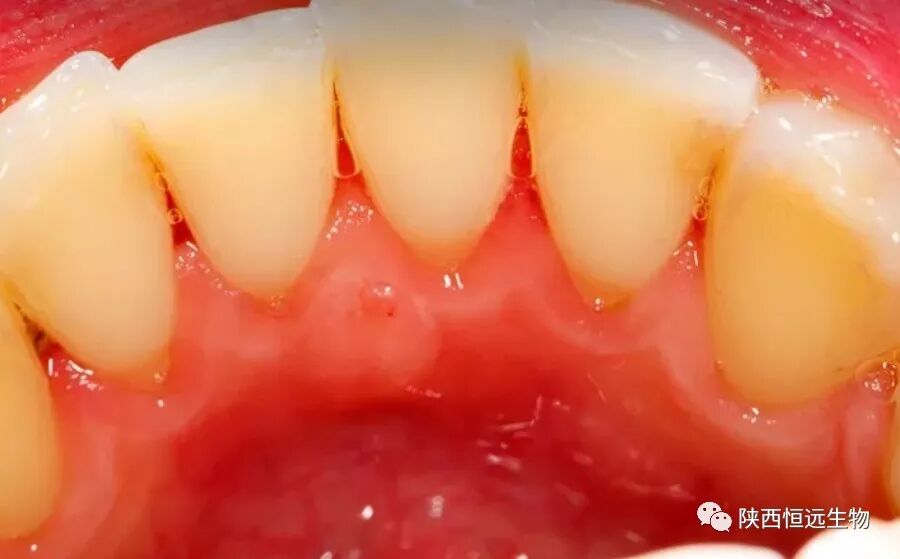

洗牙,专业的叫法是洁牙,更专业的学名叫龈上洁治术。是用洁治器械去除牙龈上牙石、菌斑、色渍,并抛光牙面,延迟菌斑和牙石沉积附着的一种医用操作护理术。是治疗牙周病最基础的手段。而牙周病,是常见的口腔疾病,也是引起成年人牙齿丧失的主要原因之一,更是危害牙齿和全身健康的主要口腔疾病!

2、超声洁治:医生会仔细对每颗牙齿的颊/舌侧、近远中面、龈上龈下部分均清洁干净。洁治过程中会有轻微酸痛(牙本质过敏症状),偶有出血症状,牙周环境越差,出血越明显(类似早晨刷牙牙齿出血)。

洗牙前      VS      洗牙后